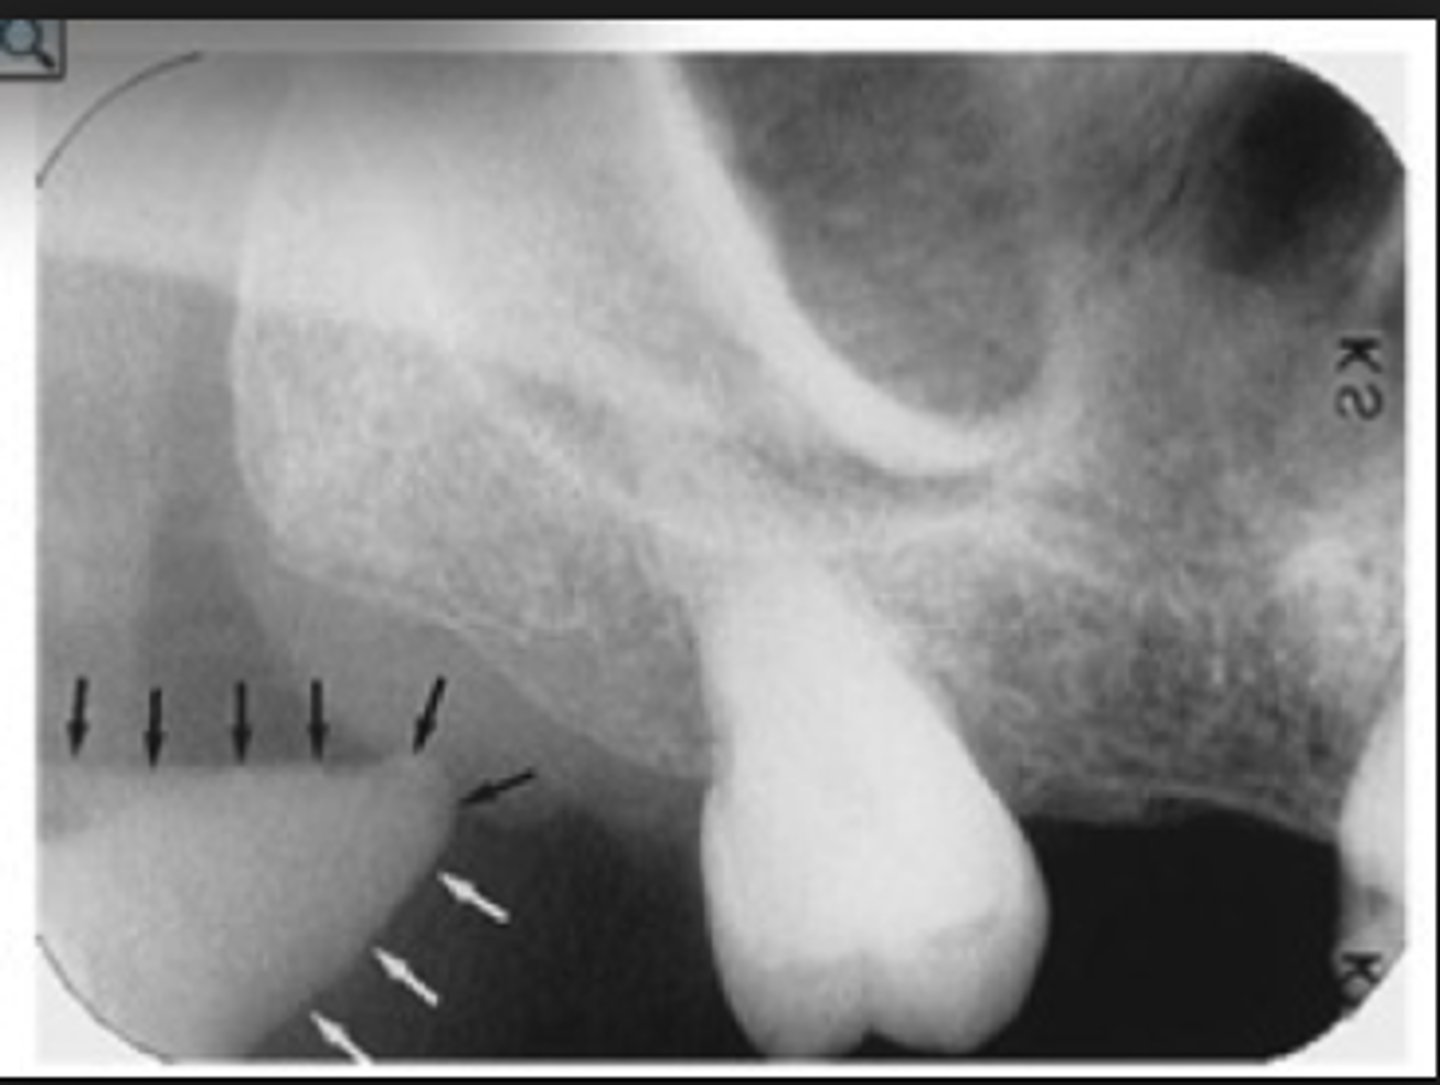

Anterior border of the ramus

What is the radiopaque structure seen here?